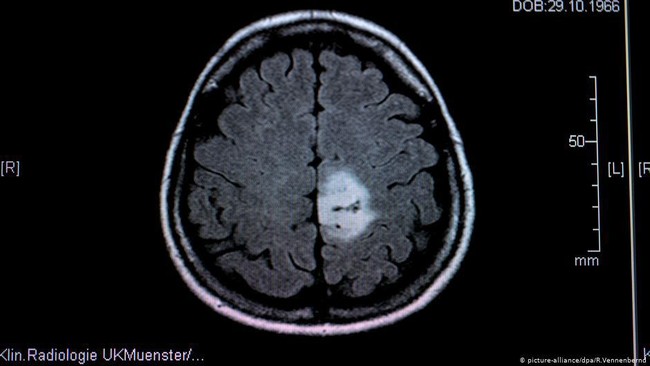

Ilustrasi tumor otak | Foto: DW (SoftNews)